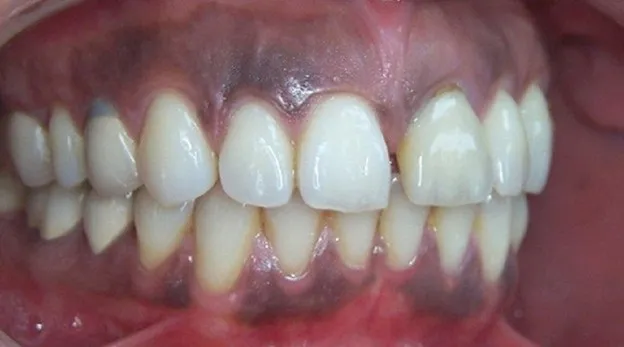

تغییر رنگ لثه بعد از ایمپلنت معمولاً واکنشی طبیعی بدن به جراحی و تغییرات بافتی در محل کاشت دندان است. در بیشتر موارد، تیرگی یا بنفش شدن لثه به دلیل افزایش جریان خون، ترمیم بافتی یا فشردگی خفیف لثه در اطراف پایه ایمپلنت است و بعد از چند روز برطرف میشود. اما اگر این تغییر رنگ همراه با درد، بوی بد دهان یا تورم باشد، احتمال عفونت یا نکروز بافتی وجود دارد و نیاز به بررسی فوری توسط دندانپزشک دارد.

در صورتی که ناحیه ایمپلنت ضدعفونی نشود یا فشار بیش از حد به بافت لثه وارد شود، ممکن است بخشی از بافت دچار کاهش جریان خون یا عفونت شود و رنگ آن به بنفش تیره یا آبی تغییر کند.

| بنفش تیره یا سیاه | بیش از ۷ روز | غیرطبیعی | احتمال نکروز یا عفونت | مراجعه فوری به دندانپزشک |

| قرمز و متورم همراه با بوی بد | در هر زمان | خطرناک | عفونت باکتریایی یا التهاب حاد | درمان دارویی یا جراحی اصلاحی |

میتواند نشانه التهاب فعال یا تجمع خون در بافتهای اطراف ایمپلنت باشد. اگر پس از یک هفته هنوز تغییر رنگ پابرجاست، احتمال فشار بیش از حد پایه ایمپلنت وجود دارد.

| تورم یا تغییر رنگ سیاه | نشانه نکروز یا عفونت پیشرفته | اقدام اورژانسی |

توصیه مهم: اگر لثه از حالت بنفش یا قرمز به آبی یا سیاه تغییر کند، خوددرمانی نکنید؛ چراکه ممکن است باعث از دست رفتن کامل ایمپلنت شود.